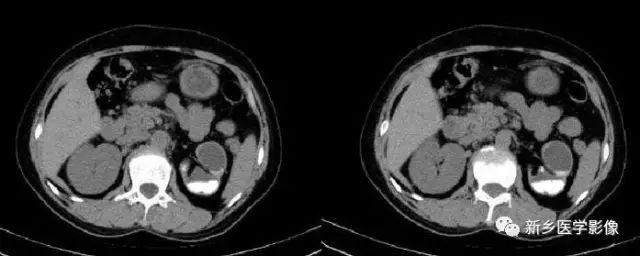

主要表现为腹腔内弥漫性的小的、多发的钙化。大小可不一致。